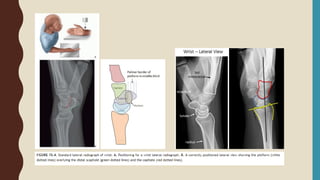

• 3 view of the wrist including true PA(PA zero), Lateral +/- Oblique

• Oblique view – useful for assess radial comminution, depression of radial styloid

• CT scan is selected in some cases ; Intraarticular fractures with multiple fragments,

centrally impacted fragments, DRUJ incongruity

CLOSED REDUCTION

• Hematoma block 8-10cc of 1% lidocaine without adrenaline in the fracture site

• longitudinal traction + wrist ulnar deviate assistant (manual) or chinese finger trap 5

kg, 5 minutes

• Increase deformity  Reverse mechanism  Reapposition  Decrease deformity

• If still have stepping, try reduction again

• arm cast/ AP slab with three point fixation (short sab/cast prefer for olderly)

• X-ray confirm